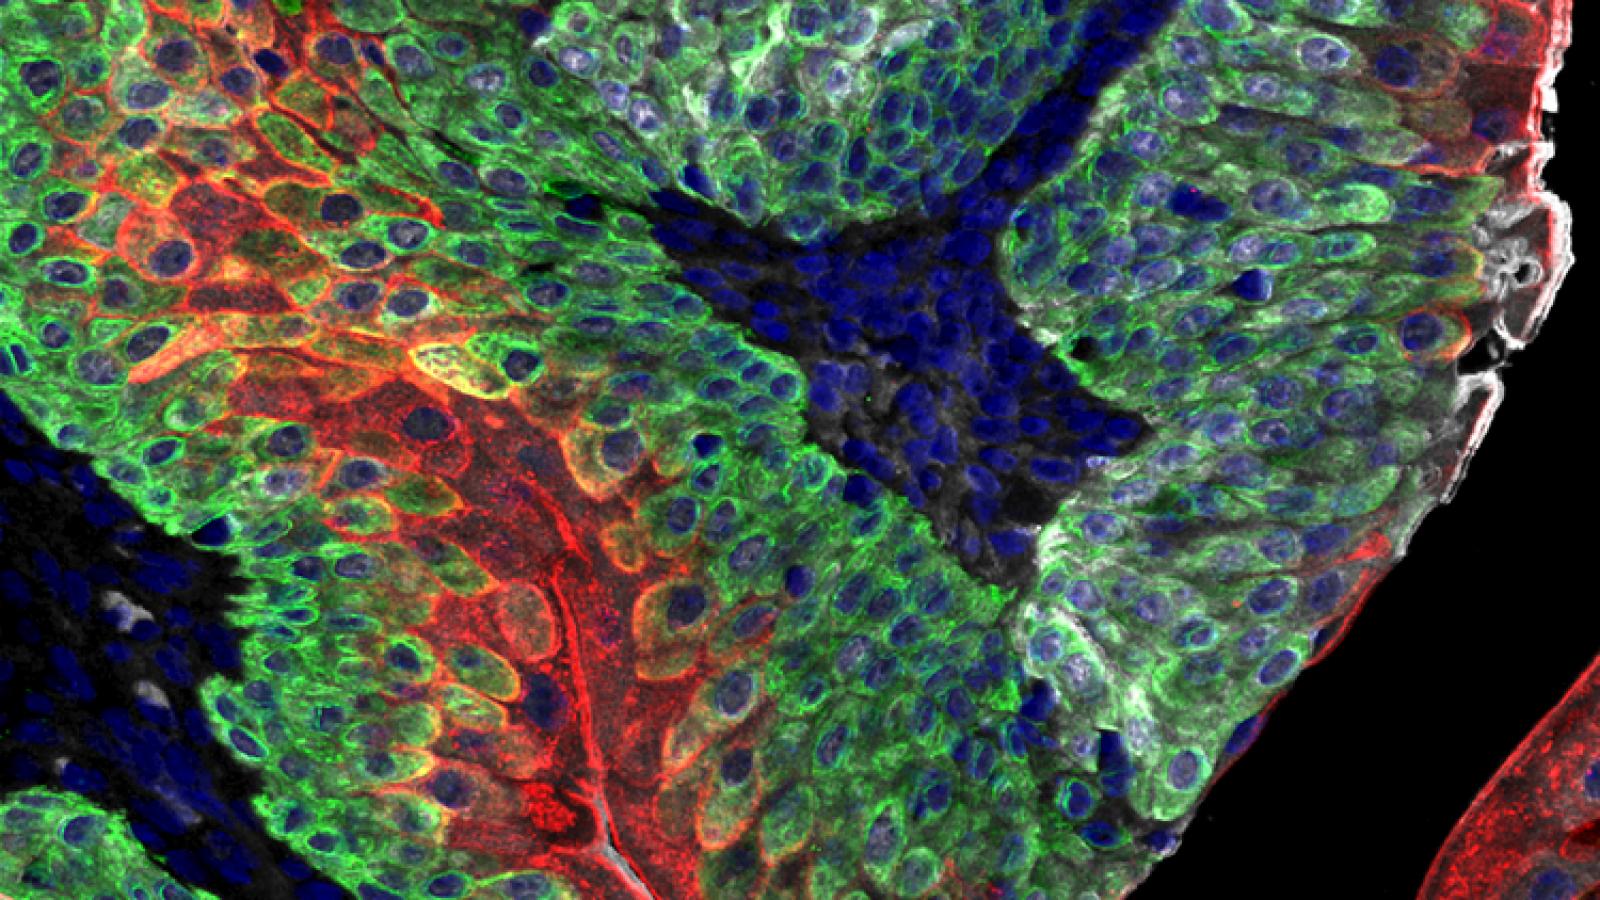

These GEMMs recapitulate the various stages of advanced prostate cancer, including castration resistance, neuroendocrine differentiation and lethal metastasis. Our GEMMs of advanced prostate cancer are based on loss-of-function of the Pten tumor suppressor gene. We have modeled Pten loss in combination with various other alleles including activation of RAF or RAS, which leads to metastatic prostate cancer (Wang et al, 2012; Aytes et al., 2013, 2017) or loss of function of p53, which leads to castration resistance that progresses to neuroendocrine prostate cancer (Zou et al., 2017). In particular, lineage-tracing of neuroendocrine prostate cancer in a GEMM based on loss of Pten and p53 provided direct genetic evidence that treatment-induced neuroendocrine prostate cancer arises via transdifferentaition, which is a specialized type of lineage plasticity (Zou et al, 2017).

Our GEMMs of metastatic prostate cancer display fully penetrant metastatic prostate cancer and shares molecular features in common with lethal prostate cancer in humans (Aytes et al., 2013). Lineage-tracing of metastases in this GEMM in vivo, combined with molecular investigations, led to the identification of master regulators of metastasis, including potential targets for therapeutic intervention (Aytes et al., 2018). Most notably, by refining our GEMM of metastatic prostate cancer we have now generated a model of highly penetrant bone metastasis. Molecular analyses of the bone metastases reveal that co-activation of MYC and RAS pathways promotes prostate cancer metastasis, and have led to the identification of a gene signature – called META-16 – that is prognostic for time to metastasis and predictive of treatment response in human patient cohorts. Thus, analysis of bone metastasis in this unique mouse model has uncovered conserved mechanisms with potential translational significance (Arriaga and Abate-Shen 2018).